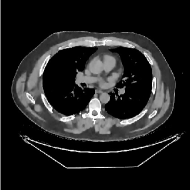

The term denotes a -based sparsification error [3, 4, 5]. We expect to be more robust to sparsity model mismatch than the -based sparsification error used in [34, 36]. Fig. 1 shows histograms of sparsification error at different outer iterations of the PWLS-ST- method. Over the iterations, the sparsification error histograms appear more like a Laplace distribution than a Gaussian distribution. This observation suggests that the proposed prior model is more suitable than the prior model for PWLS-ST-based reconstruction. Section III-B1 shows that the proposed -based sparsification error term, , improves the accuracy of reconstruction compared to the prior model in [34, 36].

This paper was inspired by a simple observation related to our recent study [34]: for the penalized weighted-least squares (PWLS) reconstruction method using prior with a learned ST (PWLS-ST-) [34], the sparsification error histograms match a Laplace distribution over the iterations; see Fig. 1. The question then arises, “Does the learned prior experience model mismatch in testing stage?” To answer this question, we aim to investigate learned STs for regularization. This paper